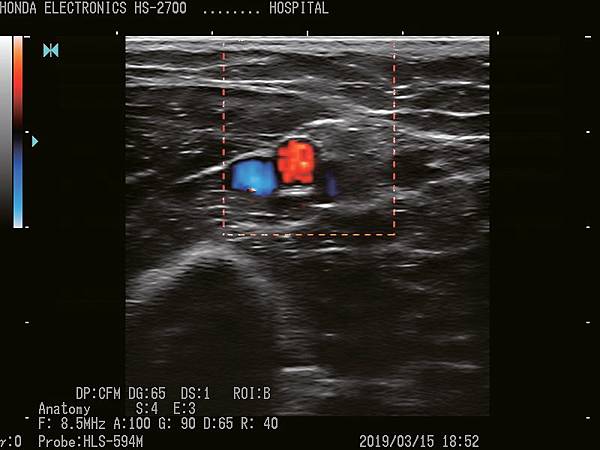

HS-2700支持CFM(彩色血流向)和PD(功率杜普勒)模式。

它們將適應廣泛的醫療應用。